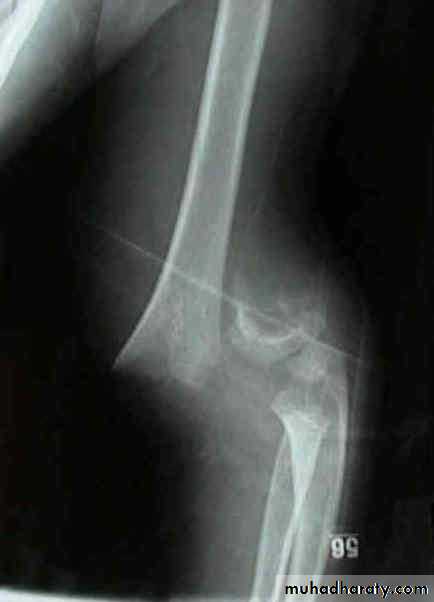

Fall on out stretched hand